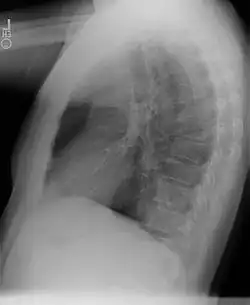

Diagnostic

Le diagnostic se fait le plus souvent dans la petite enfance, pendant les six premiers mois de vie[3], mais peut aussi être réalisé à l'âge adulte[2]. Les séquestrations extra-lobaires peuvent par ailleurs être dépistées in utero par échographie[3].

La tomodensitométrie thoracique, avec injection de produit de contraste iodé, permet généralement d'évoquer le diagnostic.